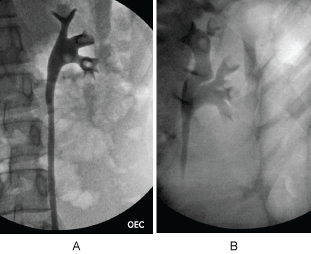

The patient underwent cystoscopy with bilateral retrograde pyelogram that revealed efflux of bloody urine from the left ureteral orifice, and filling defects in the left renal pelvic and lower pole calyx (Figure 1). The ureter was stented with a double J stent and subsequent ureteroscopy was performed. The patient was found to have renal papillae which were significantly hypertrophied and highly vascularized (Figure 2). The papilla of the lower pole calyx was hypertrophic to the point of protrusion into the renal pelvis. These hypertrophied lesions were biopsied and then ablated with a holmium laser. Pathology revealed benign fragments of renal medulla with tubular calcifications. MR angiogram performed one month later showed no vascular lesions or malformations. MR urogram showed prominent medullary pyramids in bilateral upper poles, consistent with renal papillary hypertrophy (Figure 3). The patient was followed without recurrence of hematuria for over 9 months.

Figure 1a: Left retrograde pyelogram demonstrating filling defects in renal pelvis, lower pole and mid pole calyces. Case 1-EC.

Figure 1b: Left retrograde pyelogram demonstrating filling defect in left upper pole and mid pole calyces. Case 2-AS. View Figure 1

Patient underwent cystoscopy with retrograde pyelogram that revealed a filling defect in the upper pole calyx of the left kidney, but no lesion in the bladder or contralateral kidney (Figure 1b). A double J stent was placed with delayed ureteroscopy. On ureteroscopy, all the calyces of the left kidney were congested, enlarged, and demonstrated hypertrophic papilla (Figure 2b). Active oozing of blood was seen from the papillae in the upper pole calyx, which was ablated with a holmium laser. Patient was free of hematuria on follow-up for one month. She had recurrence of hematuria with MRI and MR urogram negative for pathology other than bilateral papillary hypertrophy. Patient's symptom of hematuria resolved and she is asymptomatic for 9 months.